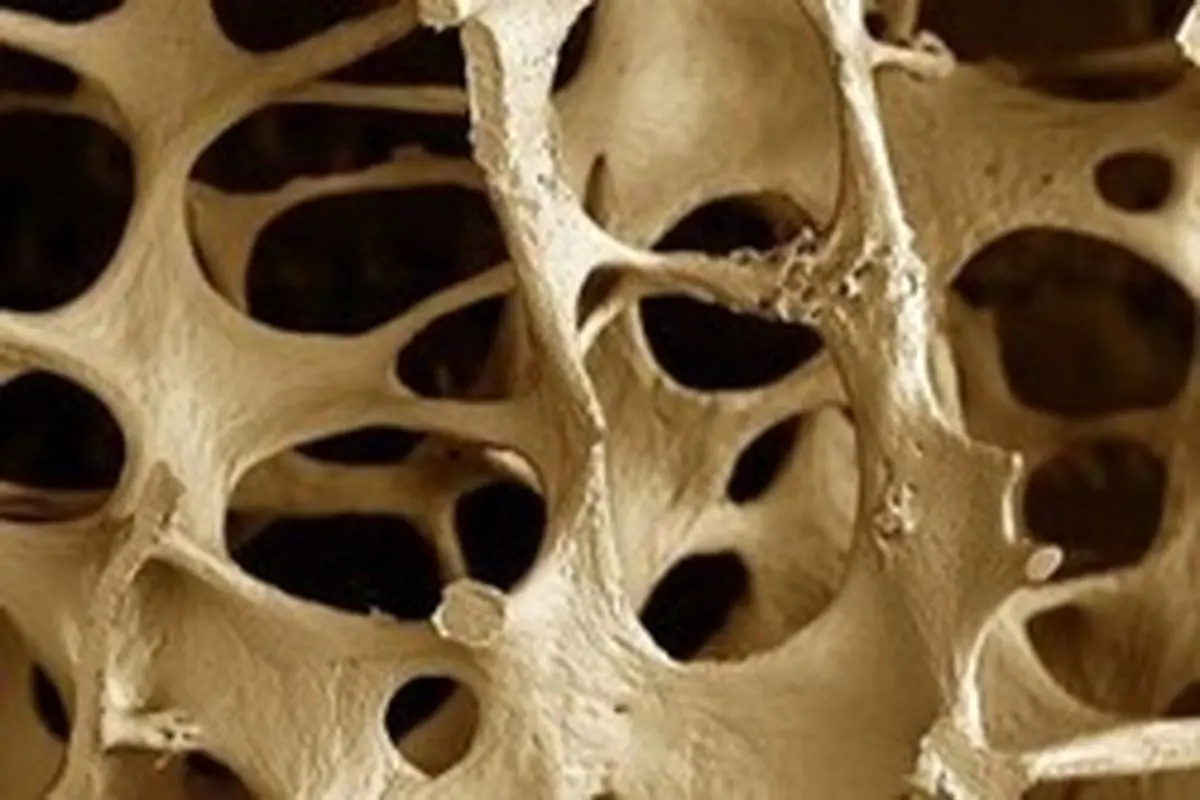

استخوانها زنده هستند

استخوانها برخلاف ظاهرشان بافتی زنده هستند که ساختار کلی بدن را مشخص کرده و از آن محافظت میکنند. در داخل استخوان فضایی برای مغز استخوان قرار دارد که در آن سلولهای خونی و نیز منابعی از مواد معدنی شامل کلسیم و فسفر تولید میشود.

در صورتی که استخوانها آسیب ببینند - چه با مداخلات پزشکی و چه به خودی خود - ترمیم میشوند. اما نکته جالب توجه این است که استخوانها بهطور مداوم از طریق فرآیندی موسوم به مدلسازی دوباره، صدمات وارده به خودشان را ترمیم میکنند. هر روز فعالیتهای فیزیکی باعث بروز پارگیها و آسیبها و شکستگیهای بسیار ریز و جزئی در استخوانها میشود که بدن به خودی خود آنها را ترمیم میکند. فرآیند ترمیم استخوان شامل تجزیه مواد معدنی و پروتئینها در قسمتهای فرسوده استخوانی و جایگزینی آنها با پروتئینهای جدید و سالم است.

چنین فرآیندی مانند قهوهای شدن سیب، روی پروتئینها هم تأثیر میگذارد. این اتصال، پروتئینها را محکم به یکدیگر متصل کرده بهطوری که انعطافپذیری آنها را دشوار میکند. این در حالی است که استخوانها به کمی انعطافپذیری نیاز دارند تا مانع تا از شکستگیهای کوچک استخوانی شوند. این اتصالات پروتئینی، استخوانها را ضعیف و شکننده میکند.

محققان بر این باورند که تجمع این اتصالات ممکن است از دلایل شکننده بودن استخوان در مبتلایان به دیابت باشد. اما این شکنندگی ممکن است علت دیگری هم داشته باشد و آن این است که مبتلایان به دیابت نوع ۲ از سطح بازسازی استخوانی کمی برخوردارند و بر این اساس، توانایی استخوانها در پاکسازی اتصالات پروتئینی کاهش مییابد. محققان بر این باورند این مشکل باعث ایجاد اتصالات بیشتری در استخوان بیماران مبتلا به دیابت میشود که احتمال شکستگی استخوانی را افزایش میدهد.

پژوهشگران در مطالعه روی استخوانهای بیماران مبتلا به دیابت نوع ۲، پی بردهاند پوسته خارجی استخوانها از اتصالات پروتئینی بیشتری برخوردار است و در نتیجه ویژگیهای مکانیکی ضعیفتری را در مقایسه با افراد غیردیابتی متحمل میشوند.